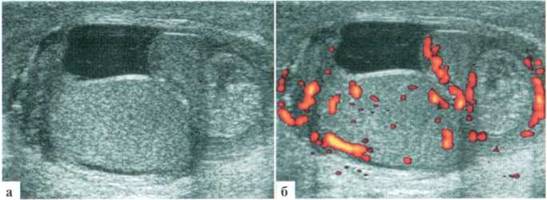

В большинстве случаев эпидидимит развивается как вторичный процесс, например при трансформации гидатиды. Однако, первичный эпидидимит все же встречается у детей всех возрастных групп, включая новорожденных. В генезе заболевания, видимо, играет роль заброс инфицированной мочи в семявыносящие протоки. При УЗИ определяются увеличение размеров придатка (всегда) и разнообразные изменения его структуры. Контуры придатка часто становятся неровными. Всегда имеет место выраженное усиление сосудистого рисунка придатка, часто — небольшое количество жидкостного компонента в оболочках (2.2.1).

Рис. 2.2.1. Эпидидимит: 1 — яичко; 2 — придаток; 3 — выпот

У детей раннего возраста изменения придатка бывают выражены еще более резко, по размерам он может приближаться к размерам яичка, форма его чаще становится неправильной. Всегда имеет место резкое усиление сосудистого рисунка (рис. 2.2.3).

Рис. 2.2.3. Эпидидимиту младенца. Придаток (2) по размерам практически одинаковый с яичком (I), резко гиперемирован